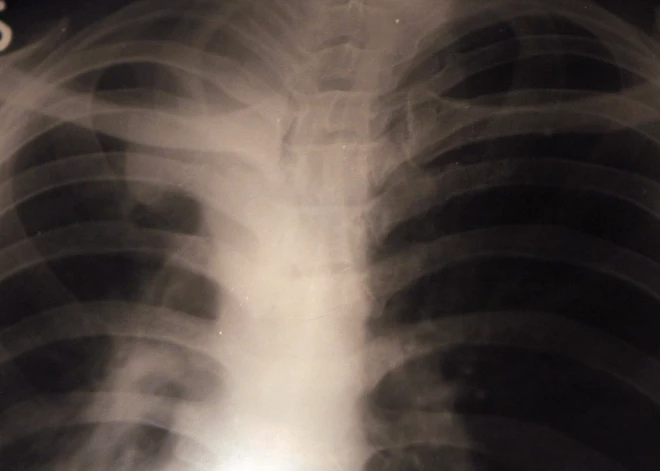

Saskaņā ar Pasaules Veselības organizācijas (PVO) informāciju, Latvijā ir otrs augstākais novēršamās mirstības rādītājs Eiropas Savienībā. HOPS jeb hroniska obstruktīva plaušu slimība, kombinējas ar citām slimībām - cukura diabētu, paaugstinātu asinsspiedienu, depresiju, osteoporozi un plaušu vēzi, un ir viens no vadošajiem riska faktoriem, kas saistīts ar novēršamo mirstību. Lai laikus atklātu HOPS, aicina iedzīvotājus bezmaksas pārbaudīt plaušu veselību, informē Rīgas 1. slimnīcas sabiedrisko attiecību speciāliste Iveta Medne.

Hronisko obstruktīvo plaušu slimību raksturo patstāvīgs gaisa plūsmas ierobežojums plaušās, kas pakāpeniski progresē pie fiziskas slodzes. Elpas trūkums ir saistīts ar hronisku iekaisumu elpceļos un noved pie elpceļu sašaurinājuma. HOPS ir viena no izplatītākajām plaušu slimībām smēķētāju vidū, attīstās vairāk nekā 50% tiem, kas smēķē ilgstoši. HOPS var izraisīt arī pasīvā smēķēšana, ja cilvēkam jāuzturas citu izsmēķētos dūmos.

Spirogrāfija ir elpošanas tests, ar kura palīdzību var noteikt, kā plaušas veic elpošanas funkciju, mērot pacienta ieelpotā un izelpotā gaisa daudzumu, un to, cik ātri pacients izelpo. Var noteikt plaušu tilpumu un to, vai elpceļos ir obstrukcija jeb sašaurinājums. Spirogrāfija ne tikai palīdz apstiprināt diagnozi, bet arī nosaka slimības smaguma pakāpi.